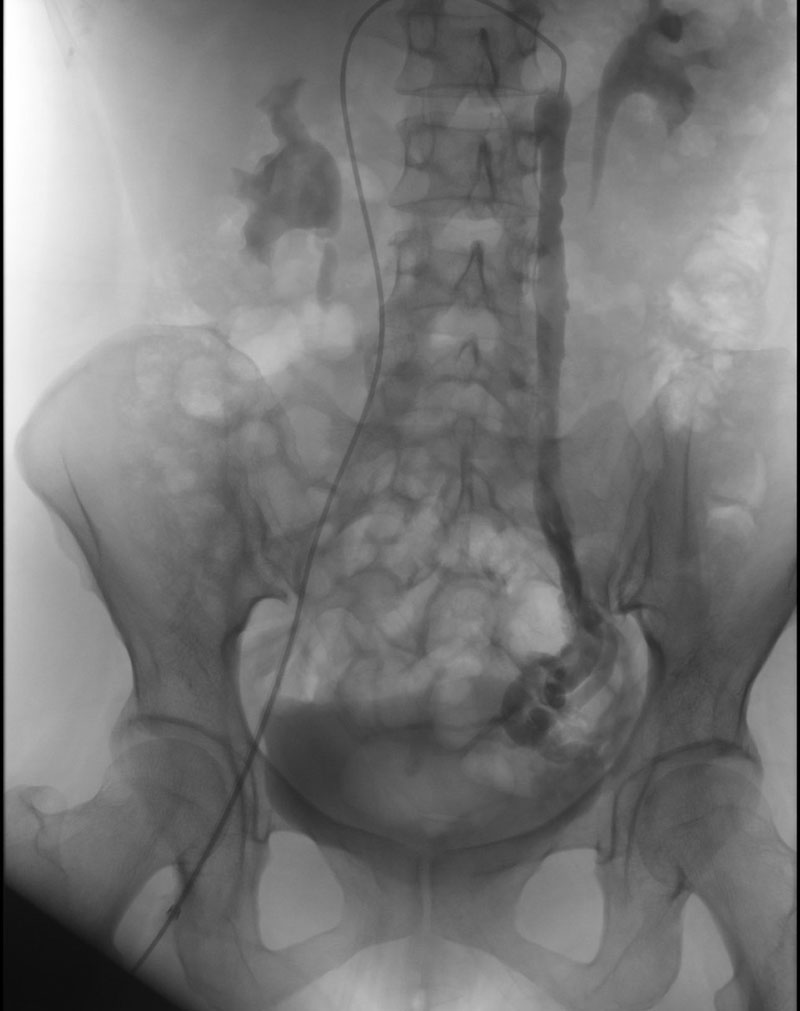

การตรวจวินิจฉัยทำได้หลายวิธี เช่น การ Ultrasound หรือ CT scan แต่การวินิจฉัยที่ให้ความแม่นยำได้มากสุดคือ การฉีดสารทึบแสงเข้าสู่หลอดเลือดดำ (Venography) ทำโดยการใช้ยาชาเฉพาะที่ แพทย์จะทำการแทงเข็มขนาดเล็ก (แผลขนาดประมาณ 1-2 มม.) ผ่านทางเส้นเลือดดำบริเวณคอ หรือขาหนีบ หลังจากนั้นทำการใส่สายสวนเส้นเลือดแล้วฉีดสารทึบแสง เพื่อตรวจสอบขนาด และทิศทางการไหลของเลือดภายในอุ้งเชิงกราน ทำให้ทราบถึงเส้นเลือดที่มีความผิดปกติ ข้อดีของการตรวจวิธีนี้คือ เมื่อแพทย์พบเส้นเลือดที่มีความผิดปกติ แพทย์สามารถให้การรักษาได้ในทันที